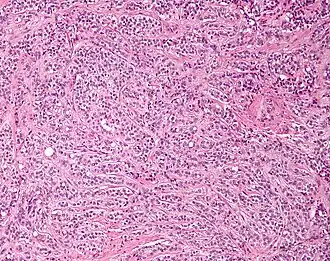

| Micrograph of a granulosa cell tumour, a type of sex-cord–gonadal stromal tumour. H&E stain. | |